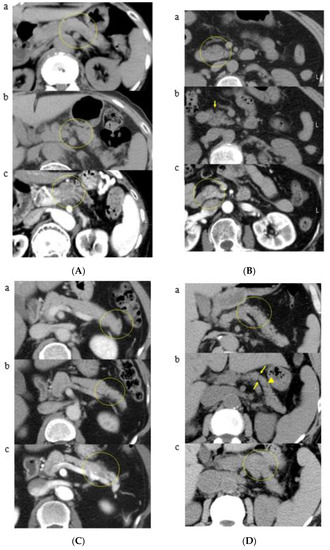

3.2. A Representative Case and Classification by Specific Abnormality of the Pancreas

| Group A | K-sign | 15 (36.6) | 5 (33.3) | 7 (46.7) | 1 (6.7) | 2 (13.3) |

| K-sign + pancreatic duct patency | 9 (21.9) | 4 (44.4) | 5 (55.6) | 0 (0) | 0 (0) | |

| Group B | Localized fatty change | 7 (17.0) | 4 (57.1) | 0 (0) | 3 (42.9) | 0 (0) |

| Localized fatty change + pancreatic duct patency | 1 (2.4) | 0 (0) | 0 (0) | 1 (100) | 0 (0) | |

| Group C | No abnormality | 9 (21.9) | 4 (44.4) | 3 (33.3) | 1 (11.1) | 1 (11.1) |